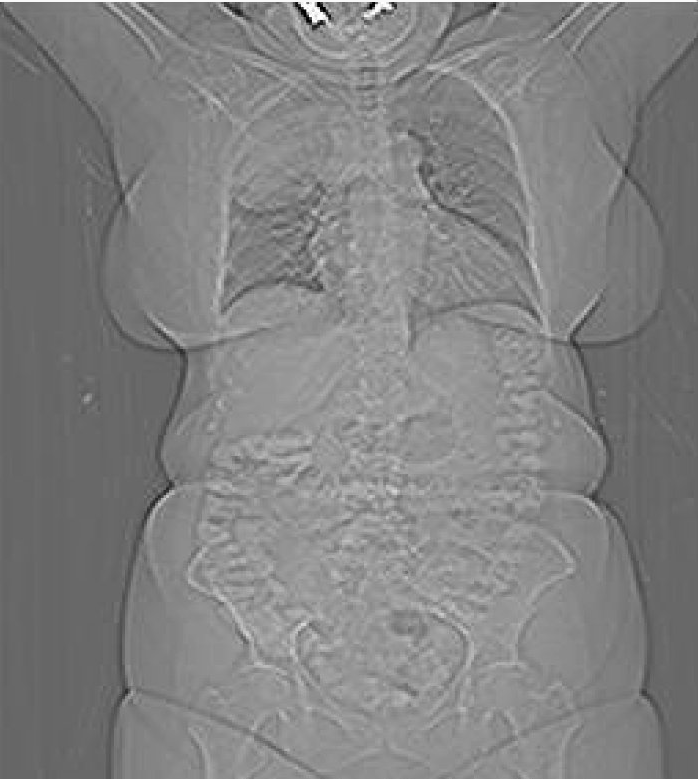

Las imágenes por TAC de los órganos internos, huesos, tejidos blandos o vasos sanguíneos, generalmente brindan mayores detalles que los exámenes convencionales de rayos X, particularmente en el caso de los tejidos blandos y los vasos sanguíneos.

Mediante el uso de equipo especializado y el conocimiento para realizar e interpretar las exploraciones por TAC del cuerpo, los radiólogos pueden diagnosticar afecciones con más facilidad, por ejemplo, cáncer, enfermedades cardiovasculares, enfermedades infecciosas, así como trastornos musculoesqueléticos y traumatismos.

Esta prueba radiológica también tiene desventajas, destacando la gran cantidad de radiación que recibe el paciente (hay que tener en cuenta que la TC de tórax equivale a unas 400 radiografías), reacciones alérgicas al contraste yodado e incluso interpretaciones erróneas (al tratarse de una imagen tan detallada, anormalidades de poca importancia y sin síntomas correlacionales pueden confundir al médico).

Tras observar las imágenes de la TC, ¿qué diagnóstico final darías?